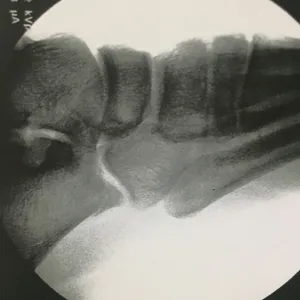

Intraop Pics Of Plantar Medial Foot Release for Chronic Exertional Compartment Syndrome in the foot